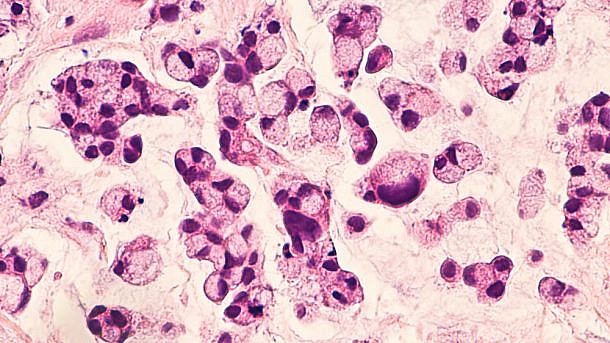

הוושט חשופה לגורמים מוטגנים פנימיים וחיצוניים כמו ריפלוקס מהקיבה, דלקת כרונית וחשיפה לקרצינוגנים סביבתיים כמו אלה שמצויים בסיגריות. המחקר הנוכחי בחן את ההשערה כי שימוש ב-NSAID מעכב את ההצטברות של מוטציות נקודתיות/מוטציות החסרה או הוספה במהלך ההתפתחות הסומטית הגנטית ב-BE.

החוקרים ביצעו ריצוף אקזומים מלא ב-82 ביופסיות מתאי אפיתל ומדגימות דם תואמות מתוך מחקר חתך בו השתתפו 41 משתמשי NSAID ו-41 משתתפים אשר לא נוטלים NSAID שעברו התאמה לפי מין, גיל, עישון וזמן מצטבר בו הם השתמשו או לא השתמשו ב-NSAIDs.